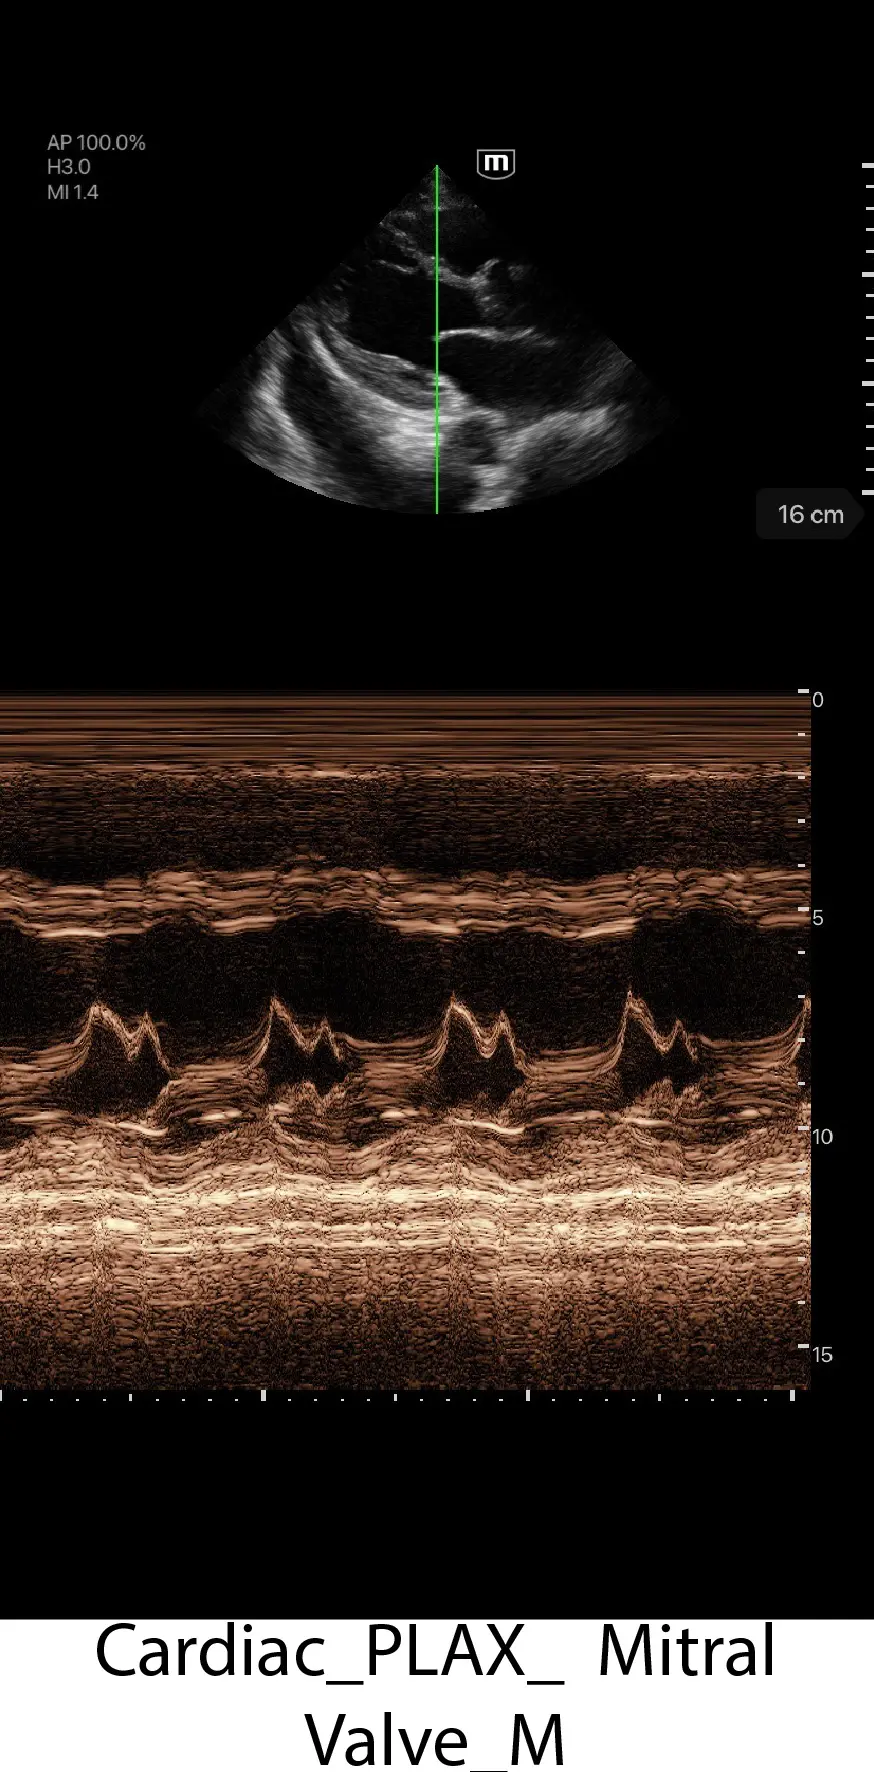

Клинични снимки